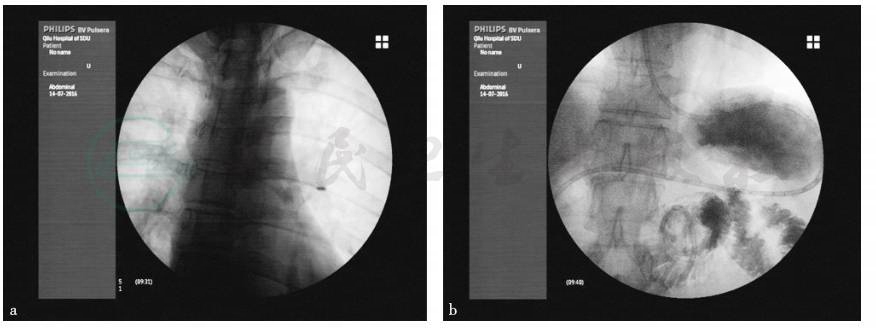

图3 X线监视下行鼻空肠管置入术

引自:主编:.消化系统疑难疾病诊疗思维及病例解析.第1版.ISBN:978-7-117-28669-5